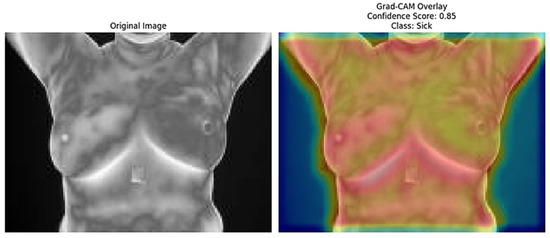

The Grad-CAM [41] overlays provide an essential layer of explainability to the ResNet152 + SVM model by highlighting regions of interest (ROI) that significantly influence the model’s predictions. These heatmaps, specific to each predicted class (e.g., normal, sick, malignant, benign), offer class-specific activation maps, shedding light on how the model differentiates among categories. By incorporating confidence scores (e.g., 0.80, 0.85) alongside these visualizations, clinicians can better understand and trust the model’s decision-making process. This approach directly addresses the “black-box” nature of deep learning models by visually explaining their predictions. Moreover, Grad-CAM overlays emphasize biologically relevant regions, such as abnormal heat patterns [56], as depicted in Figure 15, Figure 16, Figure 17, Figure 18 and Figure 19, enhancing the model’s interpretability and robustness in feature extraction. These insights validate the model’s focus areas against clinical knowledge and bridge the gap between AI-driven predictions and practical clinical applications, paving the way for greater trust and usability in real-world diagnostic settings.

Figure 16.

Grad-CAM Overlay for Sick Class (the original thermal image (left) alongside the Grad-CAM overlay (right) demonstrates the model’s focus on specific regions, leading to the prediction of the “Sick” class with a confidence score of 0.85).